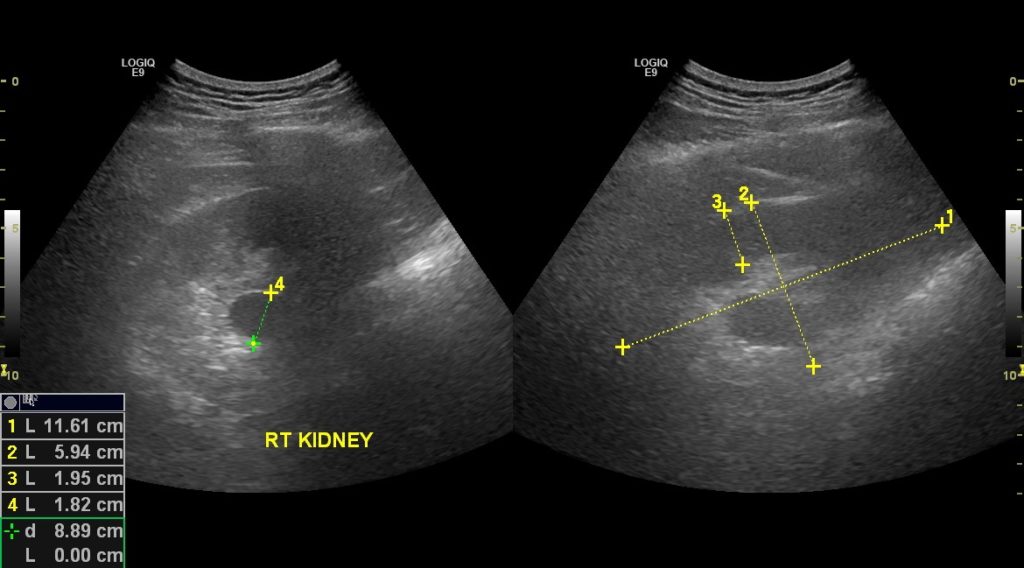

Как выглядит уплотнение в почках на УЗИ

При жалобах на тупые боли в пояснице, расстройства мочеиспускания (дизурию) врач-уролог или нефролог назначает ультразвуковое обследование органов мочевыделительной системы.Изменение эхогенности ЧЛС указывает на их уплотнение. Если стенки собирательной системы утолщаются, интенсивность отражения ультразвуковой волны от их поверхности увеличивается. Во время обследования УЗИ-специалист обязательно заметит:

- изменение размера органа;

- неровность краев;

- неоднородность тканей ЧЛС;

- уплотнение лоханки;

- деформацию чашечек.

Почка покрыта паренхиматозной тканью, которая обладает невысокой эхогенностью. Но при опухолях или воспалении эхогенность увеличивается в разы.

Заключение УЗИ-специалиста нельзя считать диагнозом. Уплотнение ЧЛС – признак патологических изменений в почке, которые вызываются множеством причин.